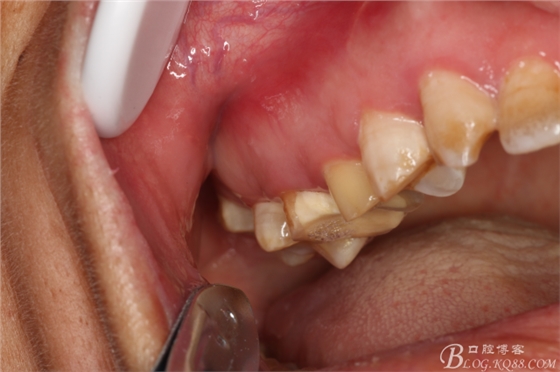

圖1.術(shù)前患者的口內(nèi)照片:15、16頰側(cè)黏膜膨隆、捫診有乒乓感

圖2.腭側(cè)未見(jiàn)膨隆,15、16合面均有白色充填物